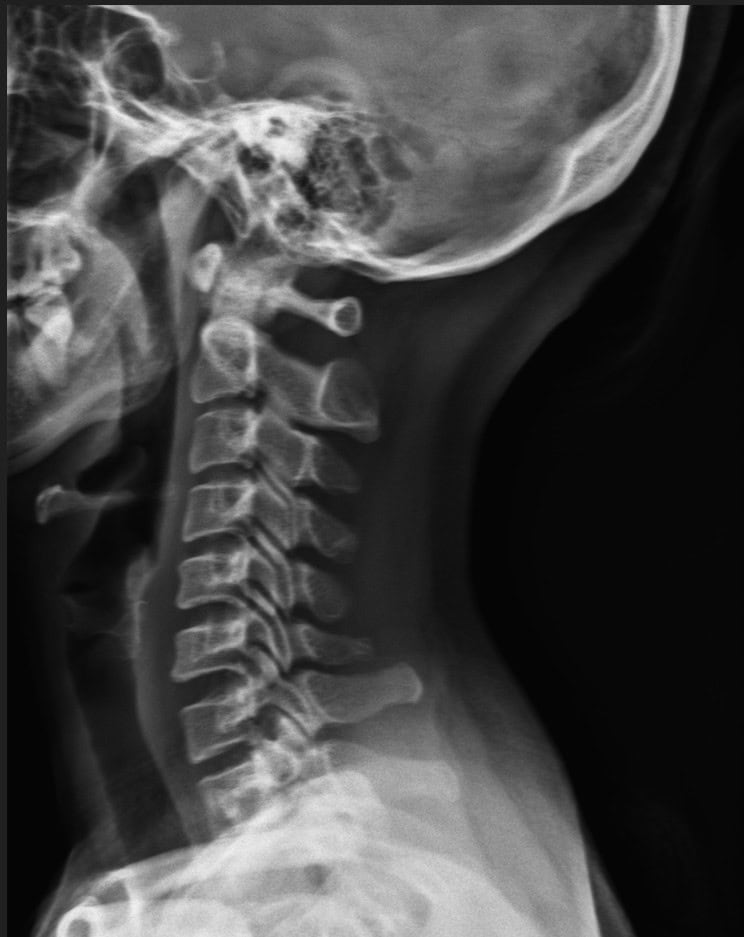

Post Scan